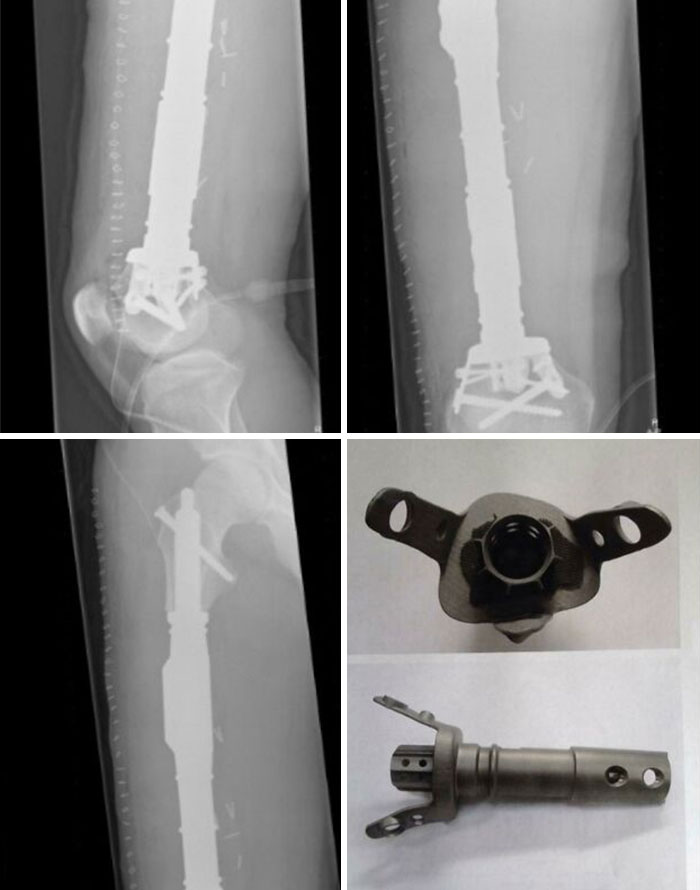

Se ve de todo en Urgencias